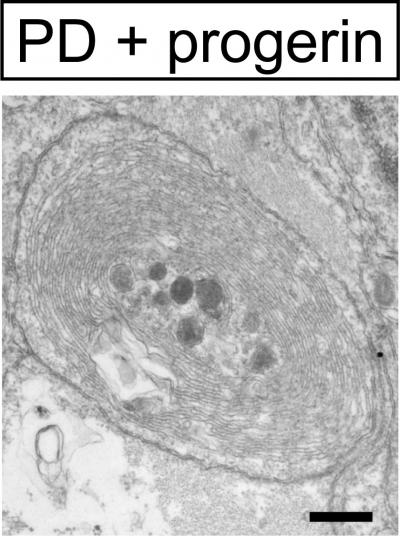

The researchers then used iPSC technology to reprogram skin cells taken from patients with Parkinson's disease and converted the stem cells into the type of neuron that is defective in these patients. After exposure to progerin, these neurons recapitulated disease-related features, including neuronal degeneration and cell death as well as mitochondrial defects.

"We could observe novel disease-related phenotypes that could not be modeled in previous efforts of studying Parkinson's disease in a dish," says first author Justine Miller of the Sloan-Kettering Institute for Cancer Research. "We hope that the strategy will enable mechanistic studies that could explain why a disease is late-onset. We also think that it could enable a more relevant screening platform to develop new drugs that treat late-onset diseases and prevent degeneration."